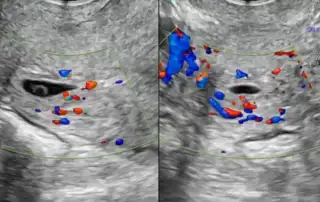

DOI: 10.36205/trocar7.2026008 - Real-Time Surgical Guidance with Robotic-Integrated Intraoperative Ultrasound in Bowel Endometriosis: A Two-Case Experience

Anshuma Shukla Kulkarni, Anushka Mehta, Riyanshi Thakur

DOI: 10.36205/trocar7.2026009 - Early Laparoscopic Excision of a Non-Communicating Rudimentary Horn Pregnancy Conceived via Transcoelomic Migration: A Video Report